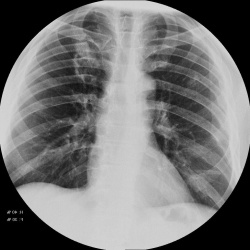

Пациент 82 года. Жалобы на одышку. Острой симптоматики нет. Есть ли патология в корне?